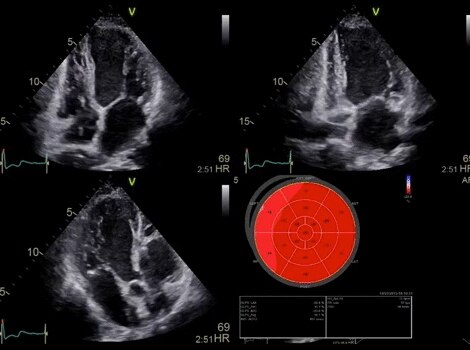

VividTM Family Cardiac Ultrasound Automated Function Imaging (AFI)

Assess left ventricular function and cardiac performance with clarity, improving clinical confidence.

Vivid™ Family Cardiac Ultrasound

Vivid E95 with cSound performance makes 4D as easy as 2D to quantify left ventricular wall motion.

Vivid™ Family Cardiac Ultrasound Automated Function Imaging (AFI)

Vivid™ Family Ultrasound

Vivid™ Family Cardiac Ultrasound with Auto EF